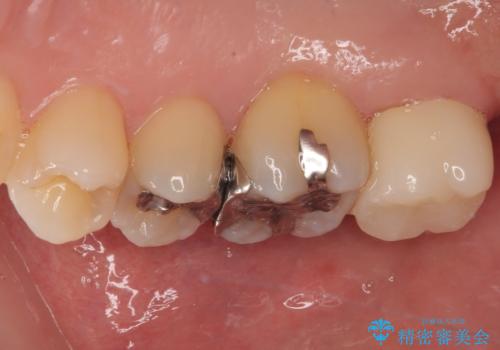

歯列が移動したとはいえ、左右ともに後方傾斜しており、むし歯の除去、形成(形を整える)、型取りの全てが非常に困難な処置となりました。

セラミッククラウンの適合はレントゲン写真からも分かる通り、境界がぴったりと合った、高適合のものとなりました。